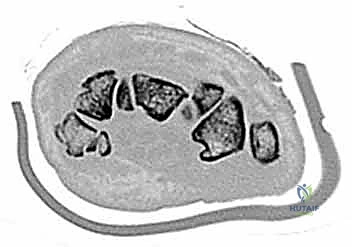

- الأشعة المقطعية (CT Scan): المعيار الذهبي لتشخيص كسور عظام الرسغ المخفية وتحديد حجم التفتت والتزحزح.

يتكون الرسغ من ثماني عظام صغيرة تُعرف بعظام الرسغ (Carpal bones)، مرتبة في صفين (صف قريب وصف بعيد). بينما يستحوذ العظم الزورقي (Scaphoid) على النصيب الأكبر من الكسور والاهتمام الطبي، فإن العظام السبعة الأخرى تلعب أدواراً حاسمة لا تقل أهمية.

- العظم شبه المنحرف (Trapezoid): عظمة محمية جداً، وكسورها نادرة للغاية، وتحدث غالباً بسبب صدمات عنيفة جداً.

- العظم الكبير (Capitate): أكبر عظام الرسغ ويقع في المركز. كسوره تتطلب قوة كبيرة وتترافق غالباً مع إصابات أخرى.